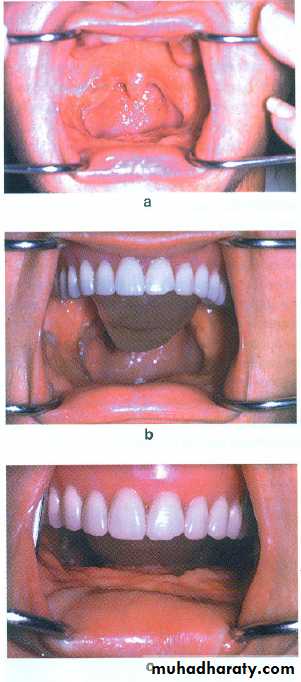

In total glossectomy, the mandibular tongue prosthesis is the treatment of choice, but in situation involving:

complete edentulous patient and an irradiated, desorbed mandibuler ridge or patient with very week abutment, Maxillary TP / PAP should be considered.

The modified maxillary denture replaces the tissue volume lost by the glossectomy and will assist the patient in swallowing.

By wax that modified intraorally until maximum contact is developed with the floor of the mouth during swallowing, then processed in acrylic resin